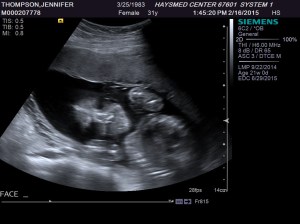

My current experience is that I continue to get hungrier and hungrier, but I have less and less space to hold anything extra. That’s good, because my baby is growing big and strong, but it is getting more uncomfortable every day. Even though I am feeling less and less like myself, I am very excited that our last ultrasound showed that we are having a little boy.